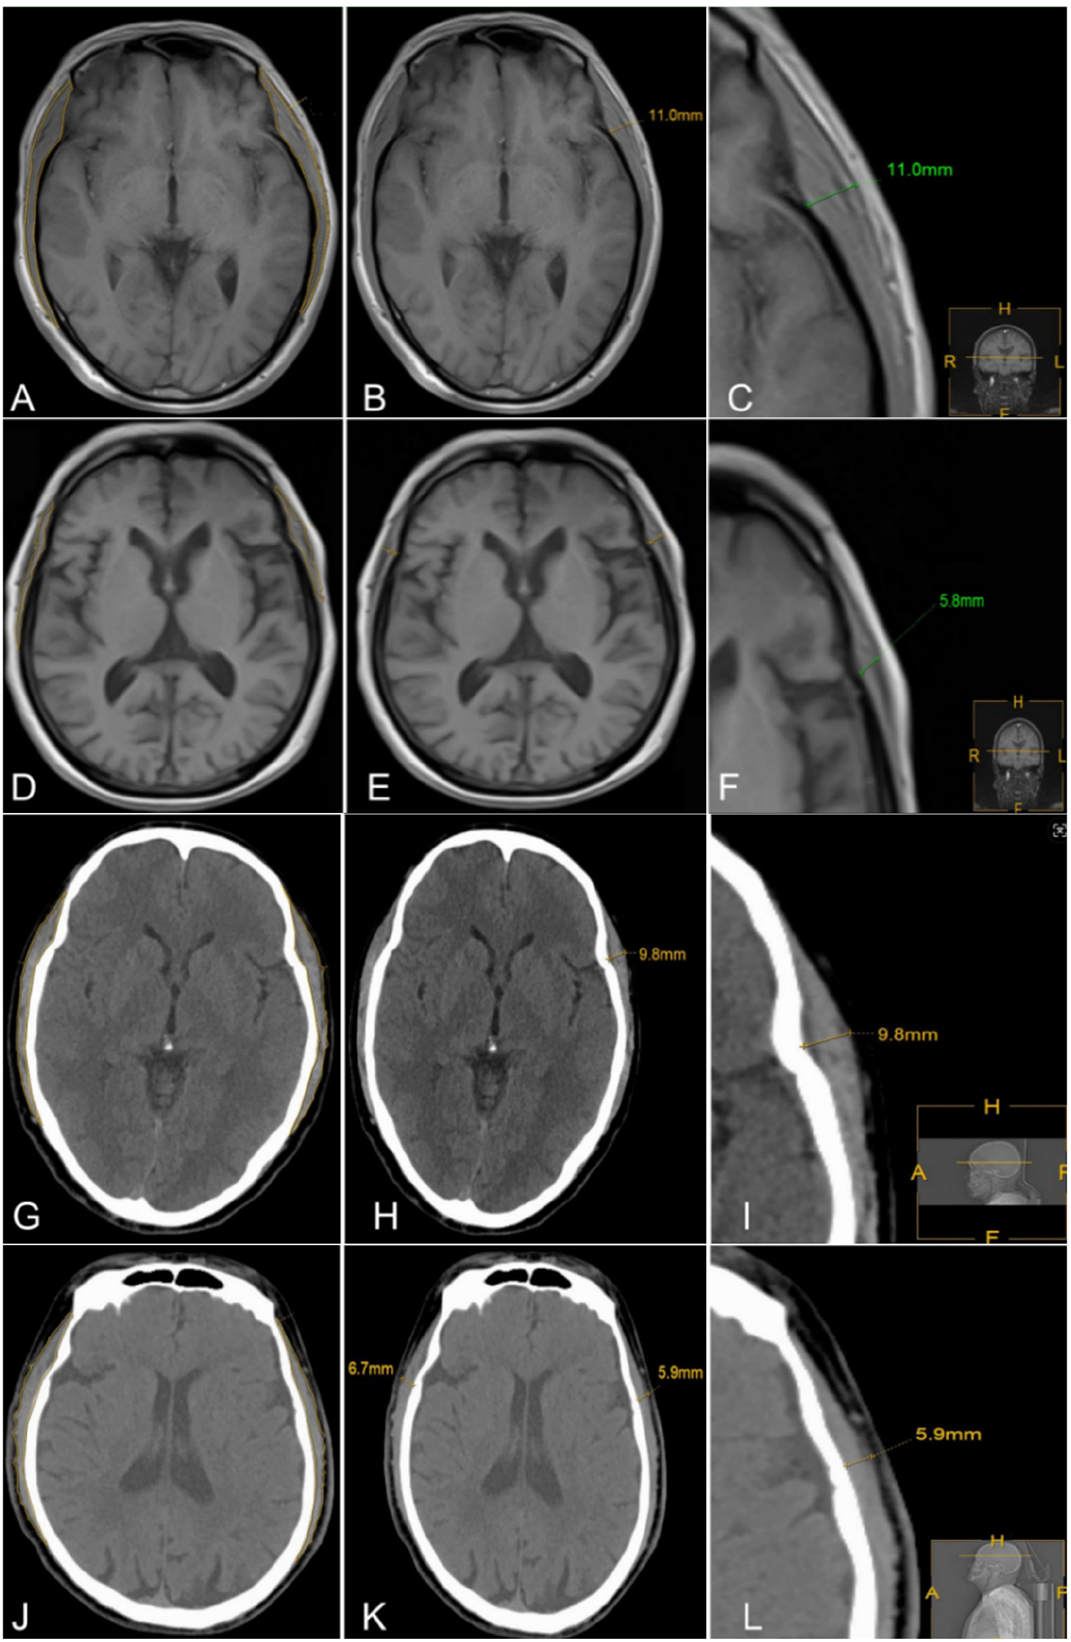

图1 颞肌横截面积和厚度的MRI、CT检查示意图注:A、B、C分别为无肌肉衰减症患者MRI T1加权成像(T1WI)影像的颞肌面积勾画示意图、左侧颞肌厚度及左侧颞肌厚度放大图;D、E、F分别为存在肌肉衰减症患者MRI T1WI影像的颞肌面积勾画示意图、左侧颞肌厚度及左侧颞肌厚度放大图;G、H、I分别为无肌肉衰减症患者CT影像的颞肌面积勾画示意图、左侧颞肌厚度及左侧颞肌厚度放大图;J、K、L分别为存在肌肉衰减症患者CT影像的颞肌面积勾画示意图、左侧颞肌厚度及左侧颞肌厚度放大图。

Figure 1 Sketch diagram of cross-sectional area and thickness of temporal muscle in patients with different muscle states